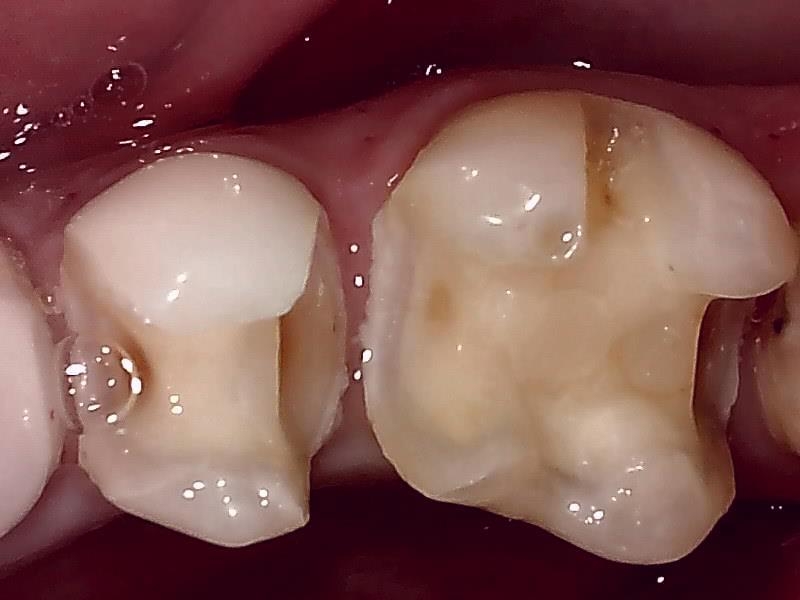

7近心隣接面の齲窩の写真